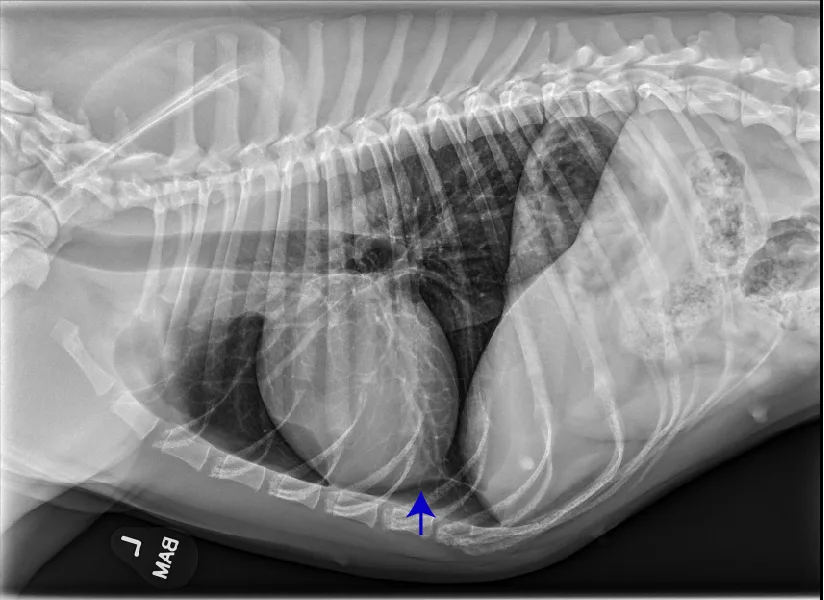

Common congenital heart diseases in dogs include pulmonic stenosis, patent ductus arteriosus, and subaortic stenosis. In addition to providing valuable information regarding the pulmonary parenchyma and vasculature, thoracic radiography may provide clues into which type of congenital heart disease is present. For example, a dog with left-sided cardiomegaly and a bulge in the ascending aorta raises suspicion for subaortic stenosis (Figure 10), whereas a dog with right-sided cardiomegaly without an MPA bulge raises suspicion for tricuspid valve dysplasia (Figure 11). Qualitative assessment of individual cardiac chambers with thoracic radiography can be an inaccurate method for diagnosis of congenital heart disease and right-sided heart enlargement in dogs. Definitive diagnosis is achieved with echocardiography.17,18 An objective parameter (ie, vertebral right heart index [VRHi]) could be a useful tool for accurate radiographic determination of right-sided cardiomegaly, although studies are needed to evaluate the influence of left-sided heart enlargement and individual breed differences in the normal range, as well as breed-specific cutoffs used for this parameter (Figure 12).19

FIGURE 11 Right lateral (left) and VD (right) projections of a crossbreed dog with tricuspid valve dysplasia. The cardiac silhouette has increased width, and the regions of the right atrium and ventricle show roundness. The cardiac apex is displaced to the left secondary to right-sided enlargement (right). The caudal vena cava (arrowheads) is dilated, and there is loss of abdominal serosal detail secondary to increased systemic venous pressures and right-sided CHF, respectively. The pulmonary vasculature is small secondary to pulmonary hypoperfusion (given significant regurgitation across the tricuspid valve and decreased forward blood flow). VHS, VLAS, M-VLAS, and VRHi collected from the right lateral view are 12.3, 2.3, 2.7, and 3.8, respectively. Images courtesy of Bruna Del Nero, DACVIM (Cardiology)